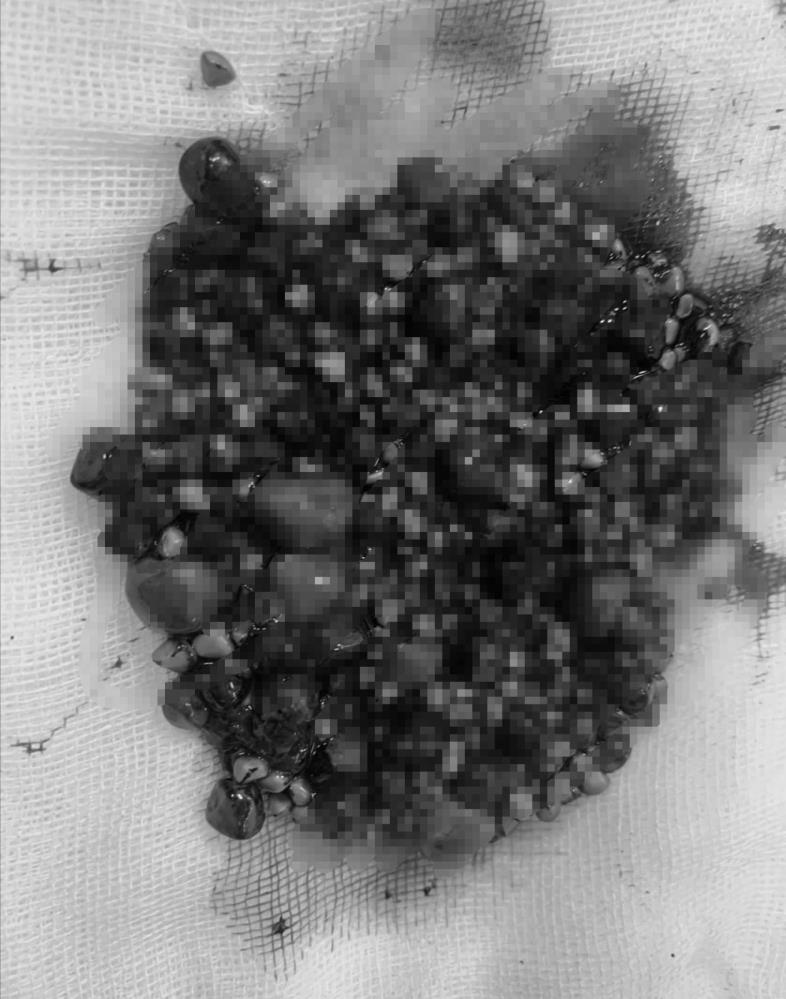

Antalya’da 42 yaşındaki Düriye Şensoy, kadın ağrısı ve şişkinlik şikayetiyle hastaneye başvurdu. Ultrasonografi görüntülemede Şensoy’un safra kesesinde taşlar olduğu saptandı. Ameliyata alınan kadının safra kesesinden tam 552 taş çıktı.

Başarısı geçen operasyonun ardından Düriye Şensoy’un safra kesesinden 552 adet taş çıkartıldı. Hastanın durumu hakkında bilgi veren Öğretim Üyesi Doç. Dr. Yılmaz Güler, “Bir saat süren ameliyat sonunda hastamızın safra kesesinden irili ufaklı boyutlarda 552 adet taş çıkarttık. Hastamızın sağlık durumu gayet iyi. Düriye hanımı hastanemizde bir gün misafir ettikten sonra taburcu işlemlerini planlamayı düşünüyoruz” diye konuştu.

Başarılı ameliyat sonrası sağlığına kavuşmanın mutluluğunu yaşayan Düriye Şensoy ağrılarının geçtiğini ve hafiflediğini vurguladı. Şensoy, “Kendimi kuş gibi hafiflemiş hissediyorum. Saframdan bu kadar taş çıkacağını hiç düşünmemiştim. Anı olarak taşlarımı saklamayı düşünüyorum” dedi.